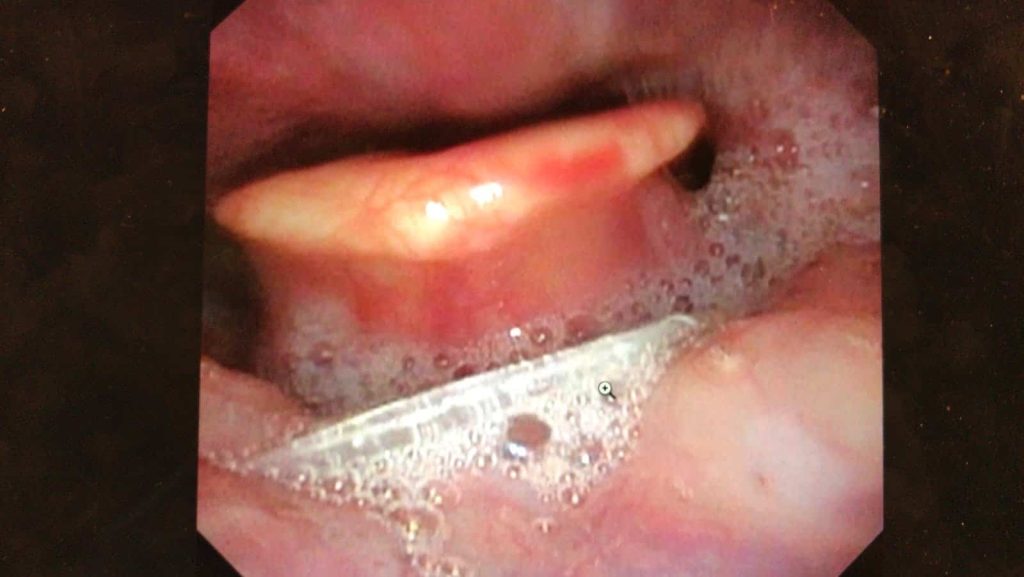

Endoscope picture of a fishbone stuck deep down in the throat

If the bone is not seen, a nasoendoscopy is done to check the deeper areas of the throat. This is a process whereby a tube with a camera attached is passed into the nose to look down the throat. Due to technological advances, the size of the nasoendoscope is small and the procedure is painless.